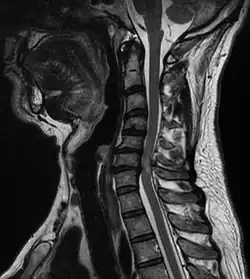

A tumour causing spinal cord compression | |

Spinal cord compression is a form of myelopathy in which the spinal cord is compressed. Causes can be bone fragments from a vertebral fracture, a tumor, abscess, ruptured intervertebral disc or other lesion.

Diagnosis is by X-rays but preferably magnetic resonance imaging (MRI) of the whole spine.[3][4]